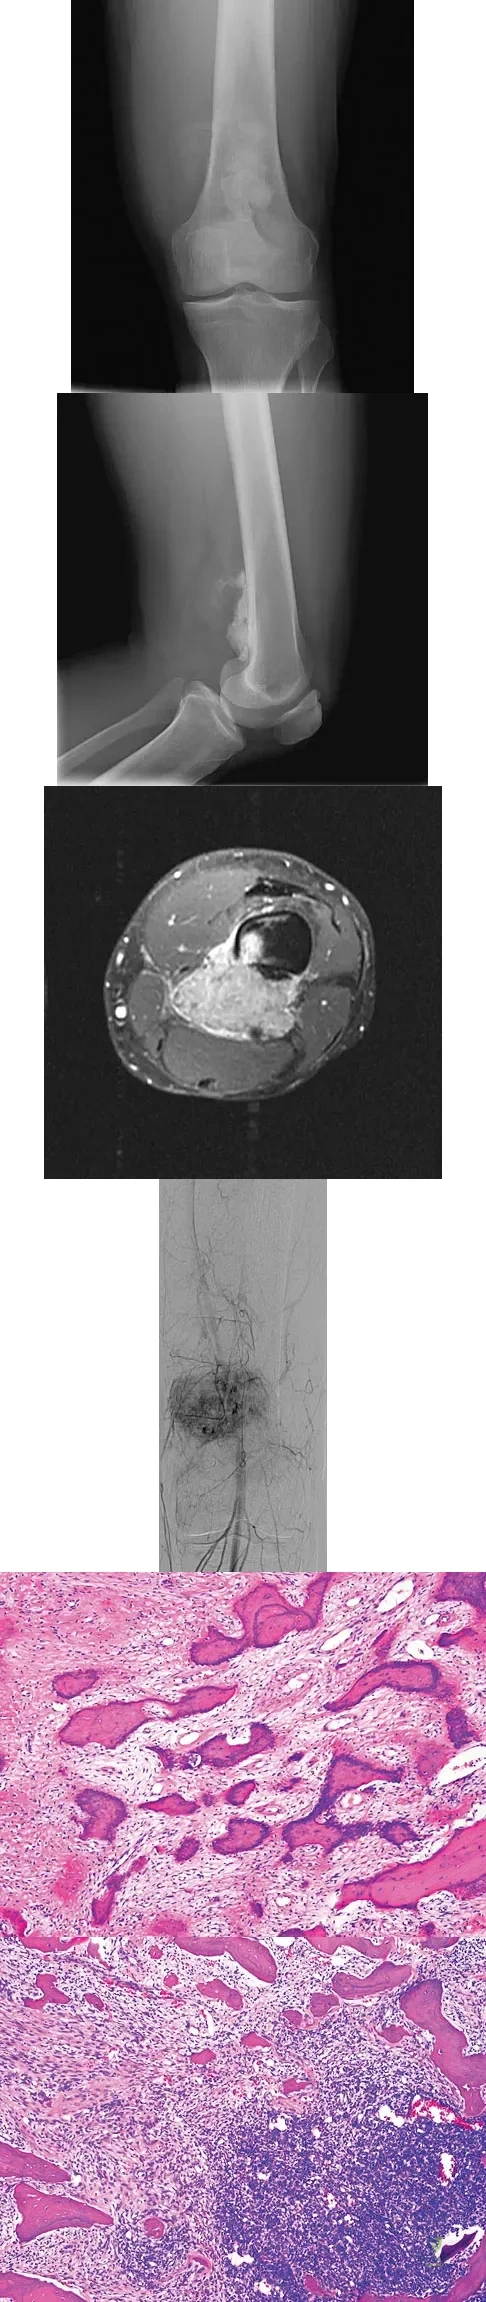

Question 69

An otherwise healthy 33-year-old man who works in construction reports a 3-month history of knee pain. Radiographs are shown in Figures 9a and 9b. An axial T1-weighted MRI scan with contrast, an angiogram, and histologies are shown in Figures 9c through 9f. What is the most likely diagnosis?

Explanation